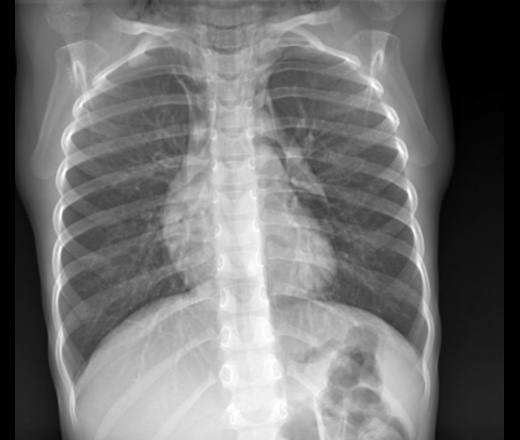

Алгоритм неотложной помощи включает срочную декомпрессию средостения через надгрудинный доступ. Техника выполнения: под местной анестезией 0,5% раствором лидокаина выполняется разрез длиной 3-4 см над яремной вырезкой грудины, затем тупым путем проводится диссекция до средостения с установкой дренажной трубки. Параллельно обеспечивается проходимость дыхательных путей — при повреждениях верхних отделов трахеи может потребоваться коникотомия.

Медикаментозная поддержка включает оксигенотерапию 100% кислородом, введение преднизолона 60-90 мг для уменьшения отека и антибиотиков широкого спектра. Статистика показывает, что при своевременном выполнении медиастинотомии выживаемость составляет 65-70%, тогда как при задержке лечения более 30 минут этот показатель падает до 15-20%. Эвакуация осуществляется в положении полусидя с постоянным мониторингом жизненных функций.